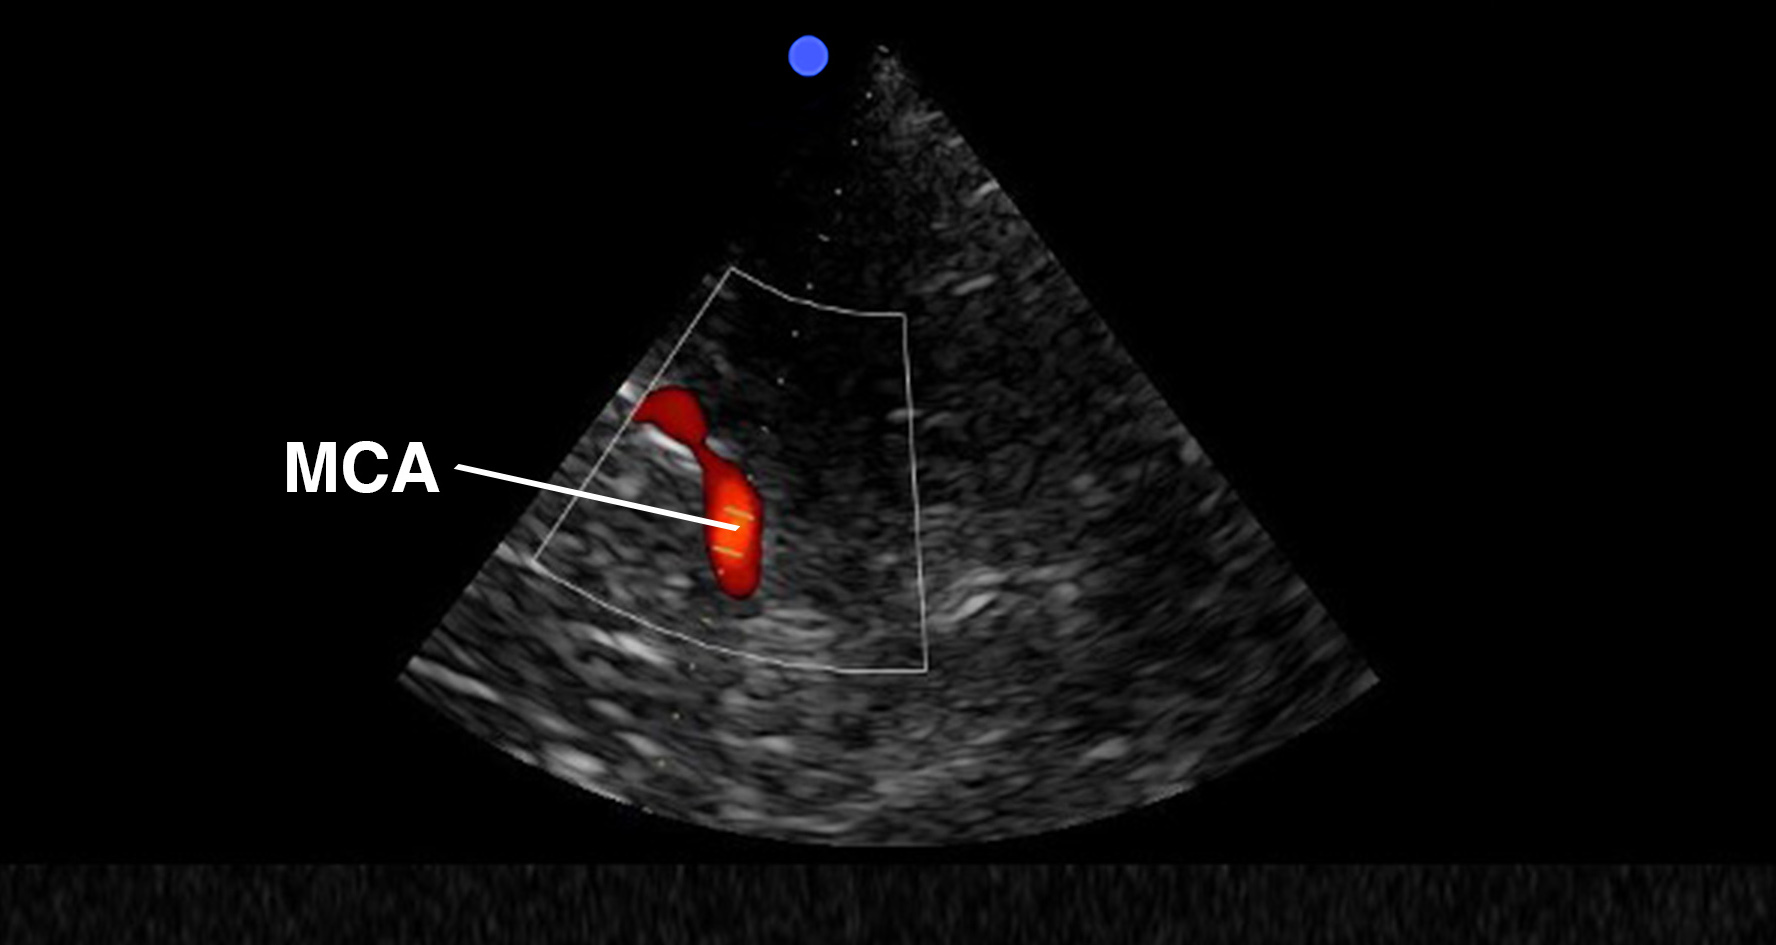

Both an in-plane and out-of-plane technique can be used, but the out-of-plane technique is preferred for peripheral vascular access. Before the actual puncture, it is best to scan dynamically to image the vein’s direction. Use the creep technique to keep the needle tip in view at all times.

Out-of-plane cannulation of a peripheral vein.